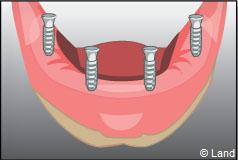

Les implants peuvent aussi servir à stabiliser un appareil amovible au maxillaire supérieur comme au maxillaire inférieur. Dans ce cas, les implants retiennent la prothèse amovible par des systèmes d’attachement.

Deux techniques sont possibles. Elles font appel à la barre de rétention ou aux boutons-pressions.